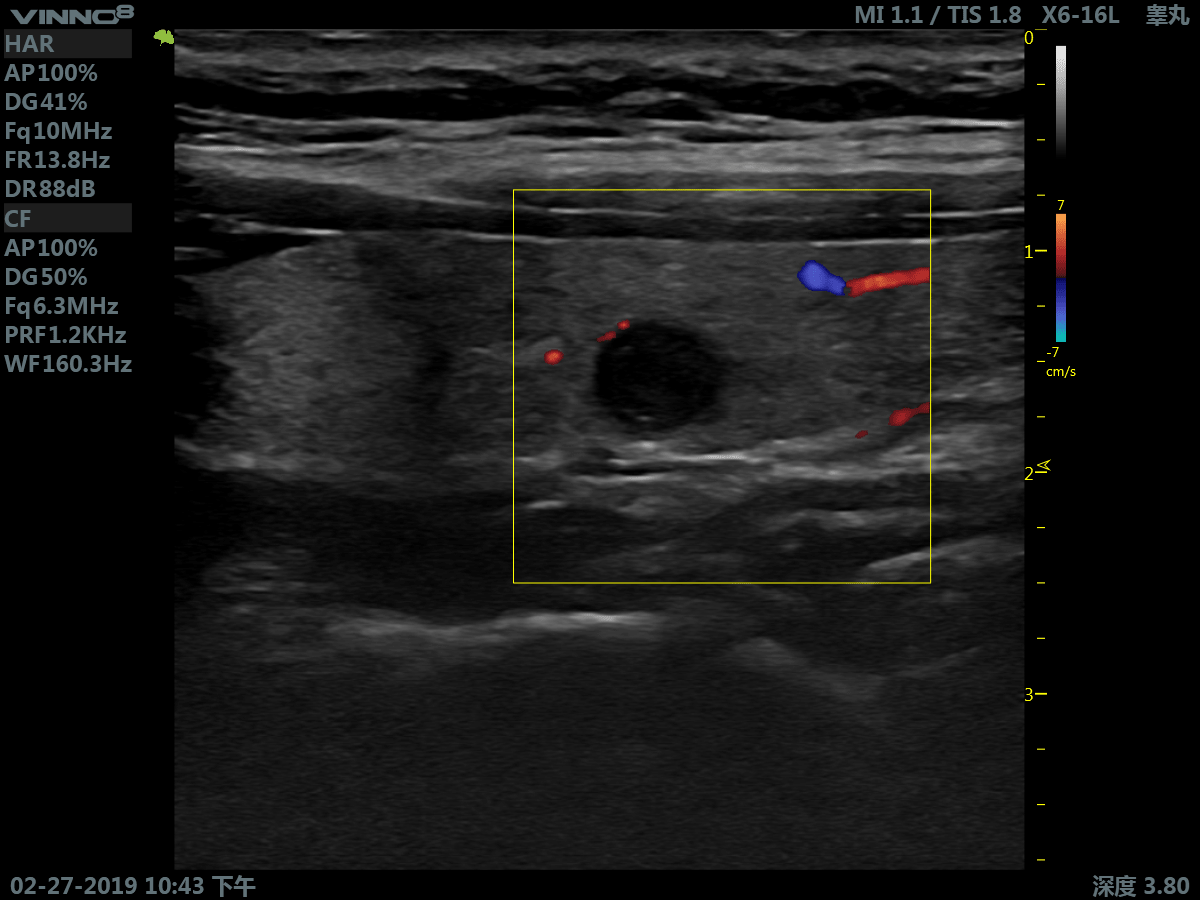

- мелкие объекты (включая щитовидную железу, молочную железу, семенники и т.д.)

- периферические сосуды

10. CFM. Режим цветового допплера

11. CFM+B (B+CF). Комбинированный режим: цветовое допплеровское картирование + В режим

12. PDI. Режим энергетического допплера.